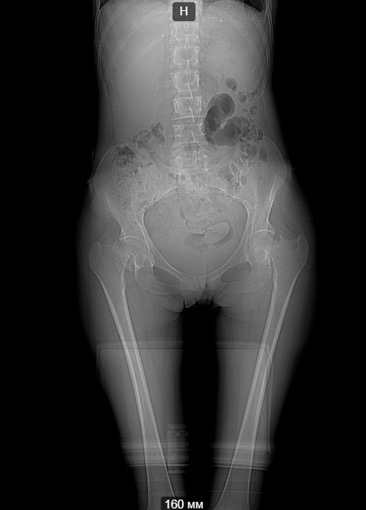

[Ortho] Патологические переломы шеек у пациентки 30 лет

Клинический случай, больная Т. 30 лет, 40 кг, анамнез: Считает себя

больной с начала декабря 2014 года, травмы отрицает, ни с чем не связывает.

Со слов на фоне полного здоровья появились отеки всего тела, после чего

боли в пояснице, правом к/с, затем т/б суставах. Обратилась за

мед.помощью по месту жительства, анемия до 40 г/л. Произведена

гемотрансфузия эр.взвесью, гемоглобин 100. При обследовании выявлена

киста яичника, с подозрением на злокачественный процесс с mts в кости

таза пациентка направлена на консультацию к онкологу. Злокачественный

процесс исключен.

Направлена на консультацию к гематологу , выполнена стернальная пункция.

Данных за миелому не получено. Больная в настоящее время проходит

дообследование с перспективой для паллиативного (а может и нет?)

протезирования т/б суставов. Из обследований: положительное RW, лечилась

10 лет назад. Гемоглобин 85, снижается, произведена гемотрансфузия до

100, формула б/о. Билирубин общ 47, прямой 9, по УЗИ, ФГС б/о.

Т-лимфоциты 60,Т - хелперы - 20. Остальное в пределах нормы, легкие

чистые. По МСКТ - дефект правой подвздошной. Как еще обследовать

больную? на что похоже? Спасибо заранее за ответы